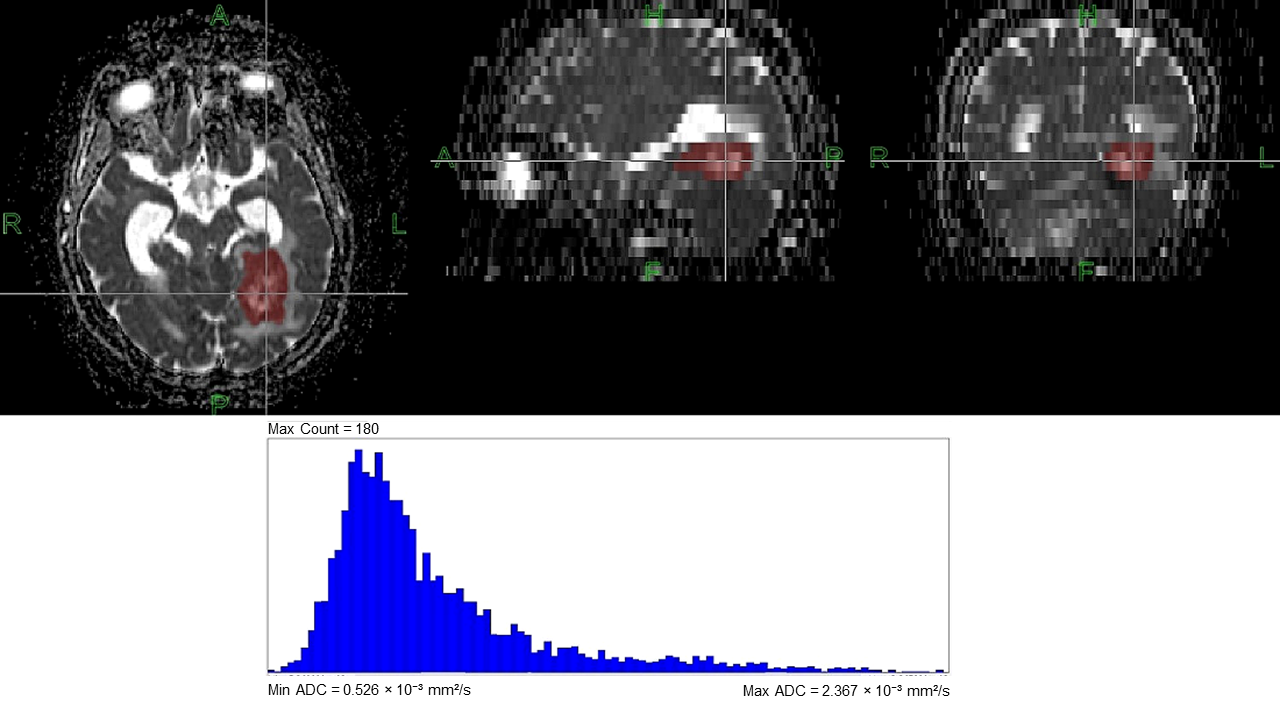

2.5. Post-Processing and ADC Histogram Analysis

2.6. Pathological Evaluation